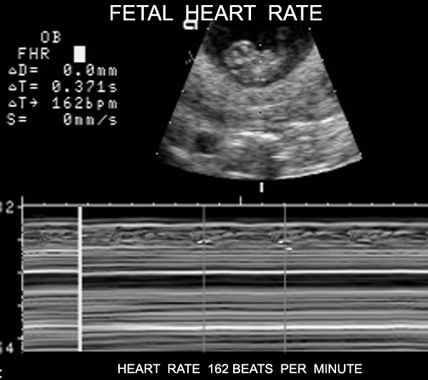

Fetal Heart Rate |

Doppler Fetal Heart |